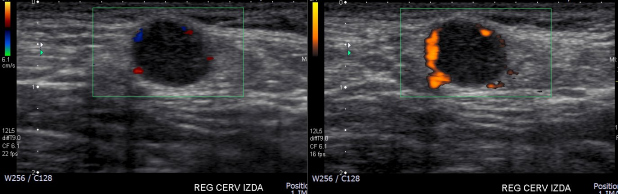

Mujer de 57 años, que consulta en diciembre de 2014 por aumento de volumen cervical izquierdo, asintomático, de 2 años de evolución. Dos ecografías cervicales de agosto y noviembre del 2012 describen adenopatía hiperecogénica, con cápsula vascularizada al Doppler color. En ecografíareciente se destaca nódulo subcutáneo de 10 mm en hombro izquierdo, bien delimitado, rodeado por una cápsula vascularizada, hipoecogénica de forma heterogénea (Figs. 1a y b). Se realiza estudio histológico mediante punción aspirativa con aguja fina de la adenopatía, la cual resulta negativa para células neoplásicas. Posteriormente se realiza biopsia incisional del nódulo subcutáneo mostrando infiltración del tejido conectivo por neoplasia que tiene caracteres morfológicos e inmunohistoquímicossugerentesde HEE con necrosis tumoral parcial.